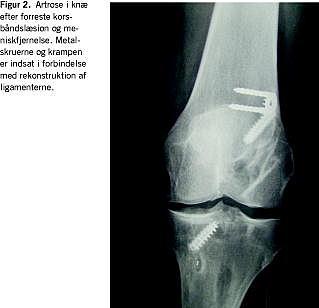

De ikketraumatiske skader i bevægeapparatet er relateret til høj belastning, mange repetitioner, bevægelse i yderstillingerne og hurtig progression af træning. Ledbrusken påvirkes negativt, f.eks. i akromioklavikulærleddet hos vægtløftere (kraftig belastning) og svømmere (mange repetitioner i yderstillinger) og i hofte, knæ og ankel hos håndbold- og fodboldspillere (formentlig mange mindre traumer med kumulativ effekt) (Figur 1 ). Resultatet er tidlig slidgigt. Blandt tidligere elitehåndboldspillere i alderen 37-54 år havde 60% slidgigt i en eller begge hofter mod 13% i en matchet gruppe [7]. Risikoen for slidgigt i knæet er også stærkt forøget hos personer med skader, der typisk opstår under idræt, f.eks. menisk- og korsbåndslæsion (Figur 2 ). I et norsk studie havde 50% af kvinderne med en gennemsnitsalder på 42 år knæosteoartrose, såfremt de havde pådraget sig en korsbåndsskade ved håndsboldspil på eliteniveau [8].